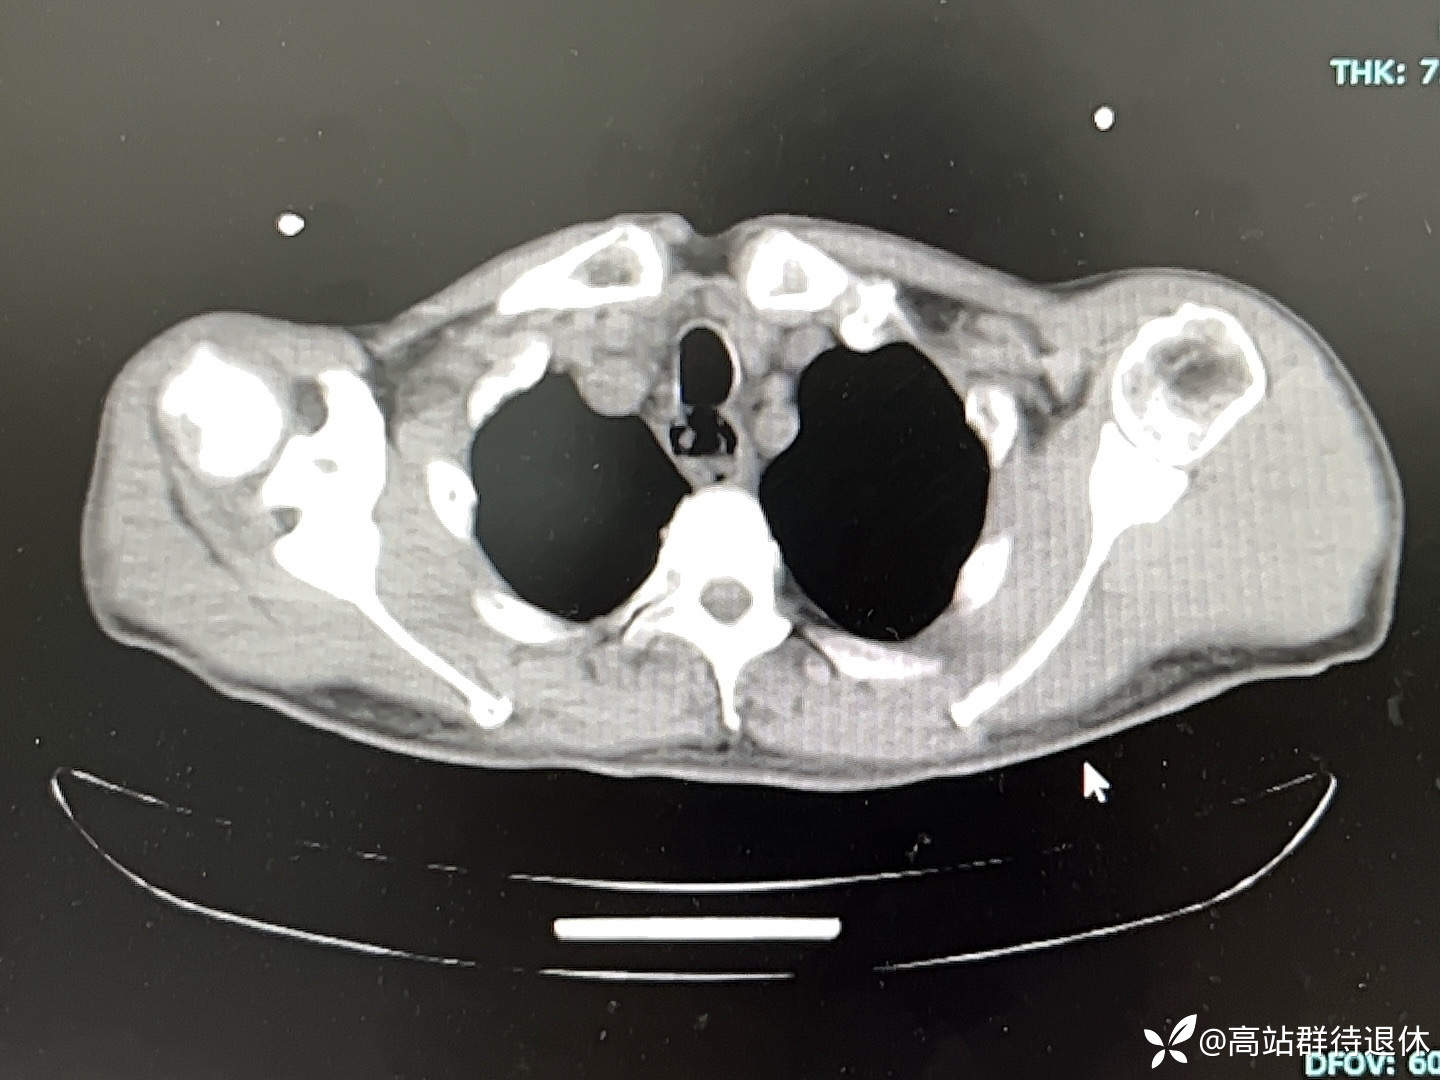

肺部CT:不提示炎症